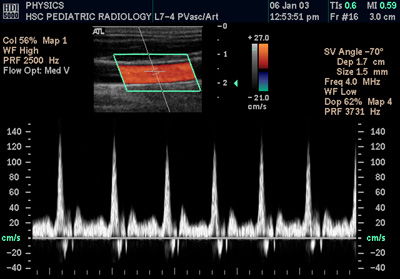

多普勒超声

多普勒超声大大提高了医学超声检查的能力,它利用多普勒效应判断某结构(通常是血流)是否朝向或背离探头运动,并计算出其相对速度。通过计算部分样本容积的频率漂移(例如心脏瓣膜上方的喷射血流),可以确定其方向、速度,并显示出来。这对心血管方面的研究特别有用,对其他的一些医学领域也是必要的,比方说诊断肝脏门脉高压症时的血流逆行。多普勒信息的图形化显示可以使用频谱多普勒,也可以使用彩色多普勒或者能量多普勒。通常此信息利用立体声扬声器表现出来:是一种虽然为人工合成,但是特征明显的声音。

严格说来,大多数现代超声仪并不使用多普勒效应来测定流速,而是依赖脉冲多普勒(PW)技术。机器发出超声波脉冲,然后再切换至接收模式。这样,接收到的反射脉冲并没有频率漂移,声学效应也不连续。但是,经过多次测量,这些序贯的测量的相变可以用来得到频率漂移(因为频率是相变的速度)。为了从发射信号和接收信号得到相变漂移信息,通常使用2种算法中的一种:自相关技术或者相关性技术。更旧的机器,采用连续多普勒(CW)技术,按上述方式显示多普勒效应。为了做到这点,机器的发射和接收换能器必须是分立的。采用连续多普勒技术的机器,其主要缺点在于不能获得距离信息(而这正是脉冲多普勒系统的主要优点——发射和接收脉冲所花的时间在知道声速的情况下可以换算成距离信息)。

在超声领域(但不是指信号处理领域),术语多普勒超声兼指脉冲多普勒和连续多普勒系统,而忽视速度测量的不同机理。

颈总动脉多普勒频谱